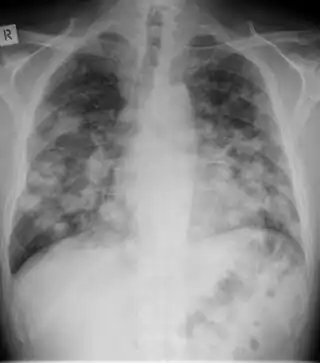

| Chest X-ray: widespread rounded lung nodules throughout both lungs | |

The extent of infection may be seen on X-ray or CT scan. On chest X-ray and CT, pulmonary aspergillosis classically manifests as a halo sign, and later, an air crescent sign.[21]